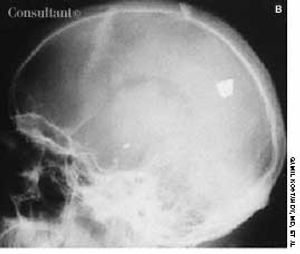

While evaluating this 26-year-old man for suspected sinusitis, skull films revealed the fragments of a 32-caliber gunshot embedded in his brain. The anteroposterior and lateral radiographs show three metallic bullet fragments; the largest remnant is on the left side of the occipitoparietal region. The patient reported being shot at age 11 but denied any residual neurologic signs.